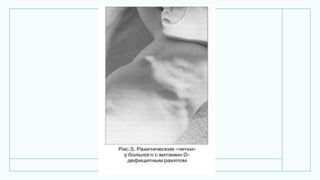

• Рентгенограмма верхньої

кінцівки дитини 7 місяців:

витончення и розгалуження

волокон кортикального шару

кісток передпліччя.

• Рентгенограмма верхньої кінцівкидитини 7 місяців: витончення и розгалуження волокон кортикального шару кісток передпліччя.